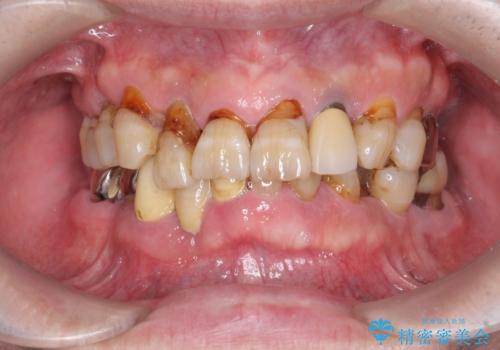

歯周病治療を伴う前歯審美セラミック治療

- 前歯の見た目をなんとかしたい、とセラミック治療を希望され来院されました。

セラミック治療を行う前に歯周病の問題を解決すべく歯周外科を行い歯周ポケットを除去し整備したのちセラミックブリッジ・クラウンの製作を行います。